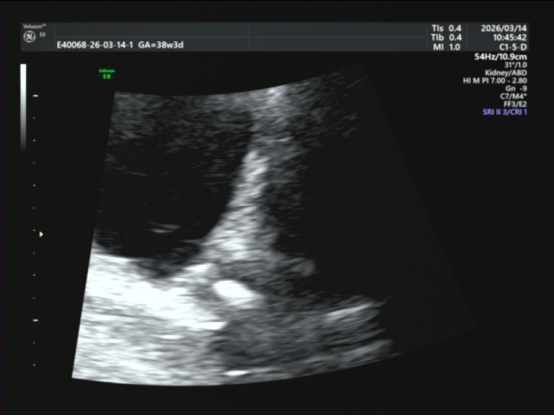

我立刻给她做了腹部超声——尿道里卡着一个强回声光团,是结石!

尿道见一强回声光团